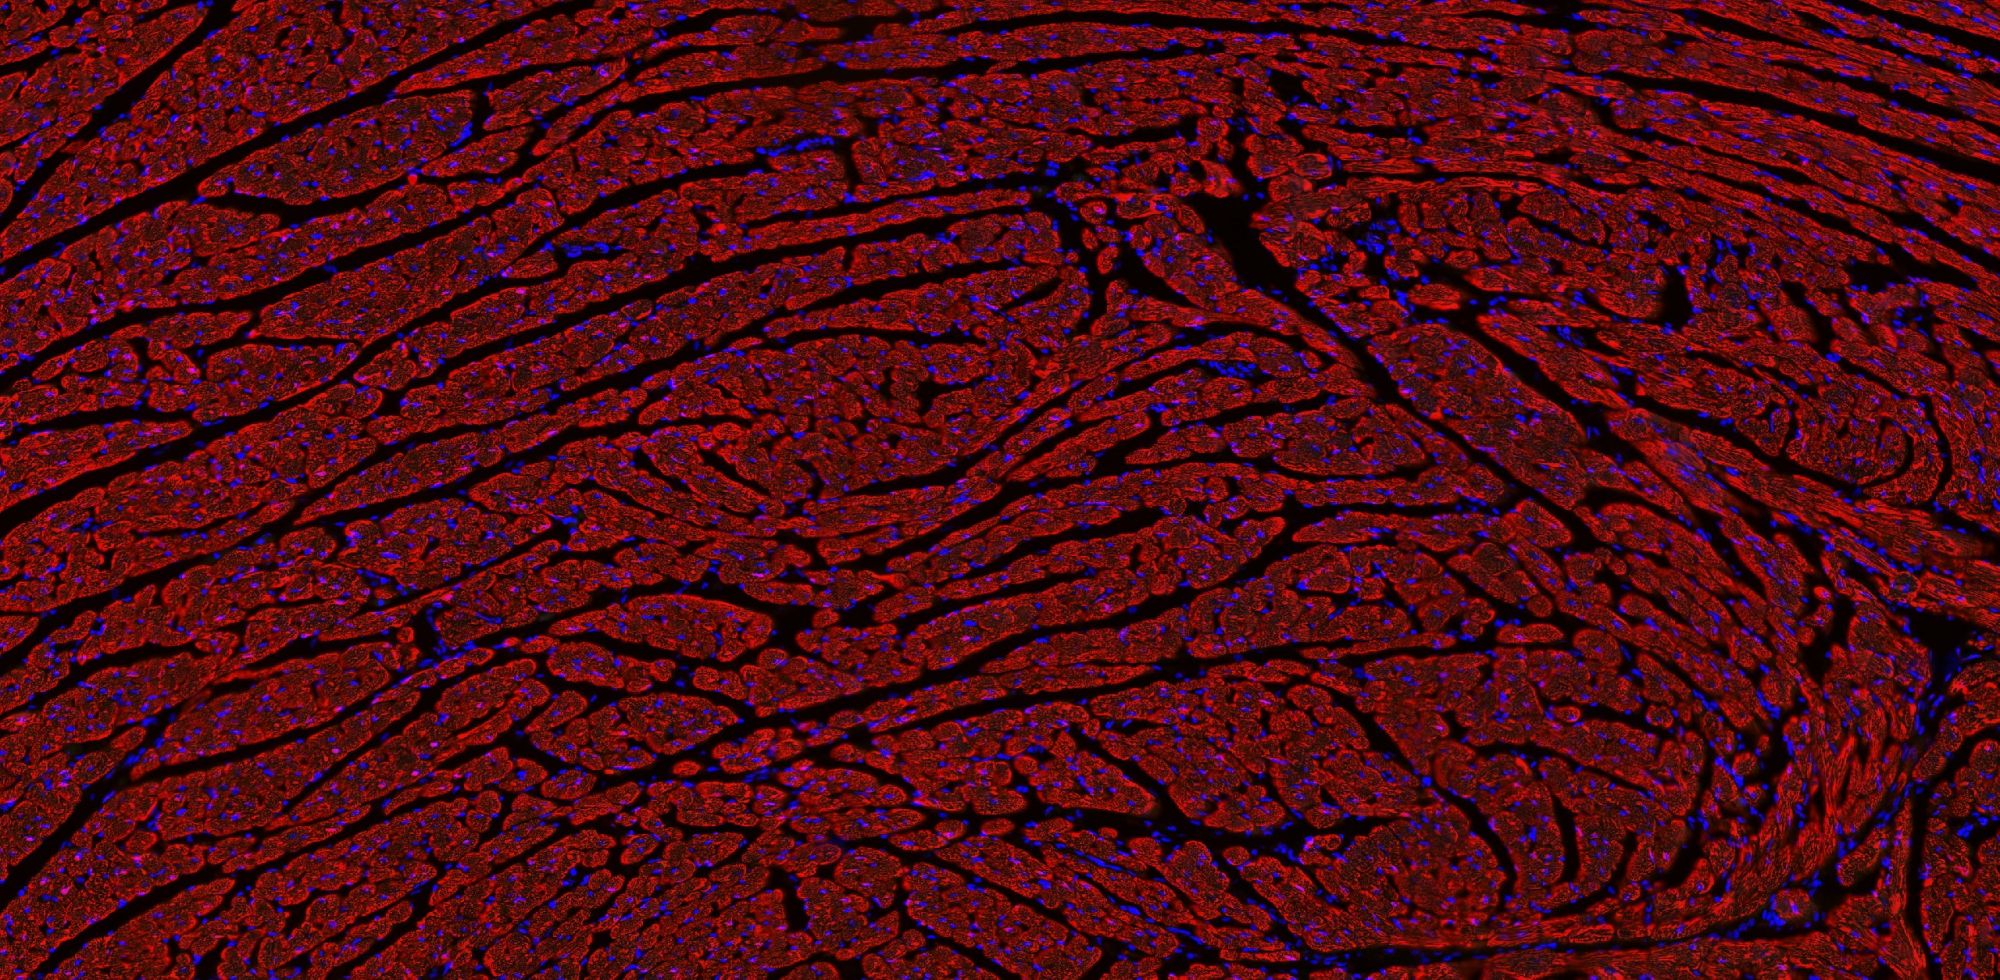

【技術(shù)原理】

免疫學(xué)的基本反應(yīng)是抗原-抗體反應(yīng)。由于抗原抗體反應(yīng)具有高度的特異性,所以當(dāng)抗原抗體發(fā)生反應(yīng)時,只要知道其中的一個因素,就可以查出另一個因素。免疫熒光技術(shù)就是將不影響抗原抗體活性的熒光色素標(biāo)記在抗體(或抗原)上,與其相應(yīng)的抗原(或抗體)結(jié)合后,在熒光顯微鏡下呈現(xiàn)一種特異性熒光反應(yīng)。

案例展示